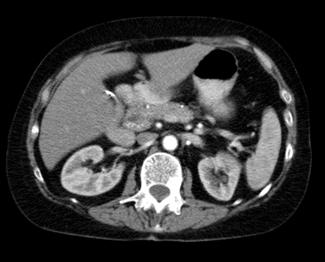

La localización del tumor se identifica con una tomografía abdominal